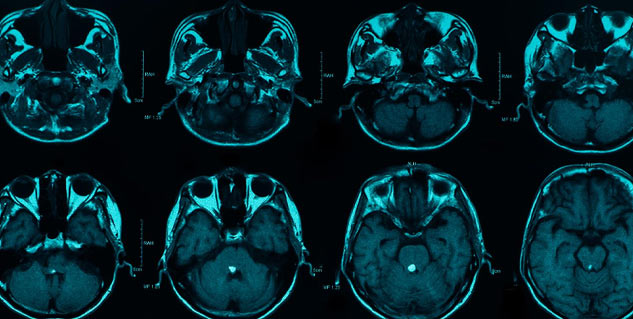

Once your symptoms are medically diagnosed, it is in the best interest that the doctor decides the treatment that suits the best. Doctors run a variety of imaging tests, such as a CT scan, which can reveal internal bleeding or blood accumulation, or even an MRI if required. A neurological exam or eye exam, which can show swelling of the optic nerve, may also be performed to gauge the best type of treatment.